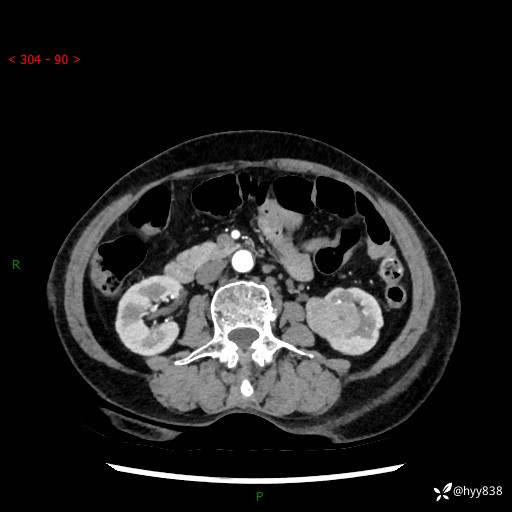

72岁/女,检查发现左肾占位1天。为了满足诊断,常规四期后,又加了延迟期-结果公布~

【患者信息】:72岁/女

【主诉】:检查发现左肾占位1天

【现病史及既往史】:患者于1天前检查发现左肾占位,无畏寒发热,无咳嗽咳痰,无腰腹部疼痛不适,无肉眼血尿、无尿频尿急症状,起病来,患者未行特殊治疗,为求进一步诊治,门诊以"左肾占位"收治入院。 发病来患者精神、饮食、睡眠良好,小便如上,大便正常,体重无明显变化。

【检查】:肾脏CT平扫+增强